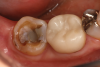

It can be disheartening to start a day in the office when the first patient presents with a mandibular second molar that requires a crown, and the gingiva is already at the height of the distal marginal ridge (Figure 1). This is the essential problem of managing short clinical crown cases: how can the crown be retained when there is limited vertical dimension for the restoration and minimal tooth structure to work with?

(1.) Example of a clinically challenging second molar preparation that has a limited vertical dimension for the restoration.

Figure 1